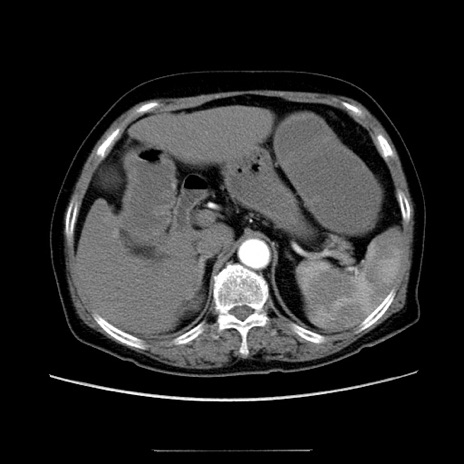

冠状断像

【症例】70歳代女性

【主訴】お腹が張る

【現病歴】1週間くらい前から腹部膨満の自覚あり。昨日夜から増悪したため、本日救急外来受診。

【身体所見】意識清明、BT 36.5℃、BP 165/106mmHg、HR 80bpm、SpO2 98%、腹部:膨満、軟、自発痛・圧痛なし、触診にて不快感あり、腸蠕動音:減弱

【データ】WBC 12600、CRP 1.04